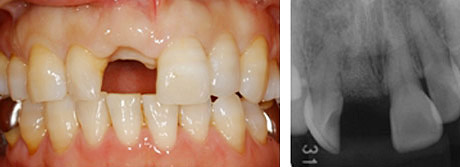

治療前:右上前歯の破折で患者さんは来院されました。

残念ながら、患歯は治療することができず抜歯になりました。以前は、このような状態をブリッジで治していましたが、きれいなとなりの歯を削ることなくこの状態を治す方法として、インプラントは優れています。